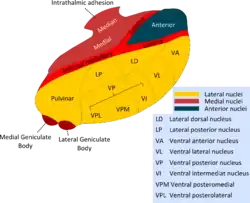

The thalamus is a paired structure of gray matter about four centimetres long, located in the forebrain which is superior to the midbrain, near the center of the brain with nerve fibers projecting out to the cerebral cortex in all directions. The medial surface of the thalamus constitutes the upper part of the lateral wall of the third ventricle, and is connected to the corresponding surface of the opposite thalamus by a flattened gray band, the interthalamic adhesion. The lateral part of the thalamus is the phylogenetically newest part of the thalamus (neothalamus), and includes the lateral nuclei, the pulvinar and the medial and lateral geniculate nuclei.[6][7] There are areas of white matter in the thalamus including the stratum zonale that covers the dorsal surface and the external and internal medullary laminae. The external lamina covers the lateral surface and the internal lamina divides the nuclei into anterior, medial, and lateral groups.[8]

Thalamic nuclei

Derivatives of the diencephalon include the dorsally-located epithalamus (essentially the habenula and annexes) and the perithalamus (prethalamus) containing the zona incerta and the thalamic reticular nucleus. Due to their different ontogenetic origins, the epithalamus and the perithalamus are formally distinguished from the thalamus proper. The metathalamus is made up of the lateral geniculate and medial geniculate nuclei.

The thalamus comprises a system of lamellae (made up of myelinated fibers) separating different thalamic subparts. Other areas are defined by distinct clusters of neurons, such as the periventricular nucleus, the intralaminar elements, the "nucleus limitans", and others.[11] These latter structures, different in structure from the major part of the thalamus, have been grouped together into the allothalamus as opposed to the isothalamus.[12] This distinction simplifies the global description of the thalamus.

The thalamus has multiple functions, generally believed to act as a relay station, or hub, relaying information between different subcortical areas and the cerebral cortex.[15] In particular, every sensory system (with the exception of the olfactory system) includes a thalamic nucleus that receives sensory signals and sends them to the associated primary cortical area. For the visual system, for example, inputs from the retina are sent to the lateral geniculate nucleus of the thalamus, which in turn projects to the visual cortex in the occipital lobe.[16] The thalamus is believed to both process sensory information as well as relay it—each of the primary sensory relay areas receives strong feedback connections from the cerebral cortex.[17] Similarly the medial geniculate nucleus acts as a key auditory relay between the inferior colliculus of the midbrain and the primary auditory cortex. The ventral posterior nucleus is a key somatosensory relay, which sends touch and proprioceptive information to the primary somatosensory cortex.